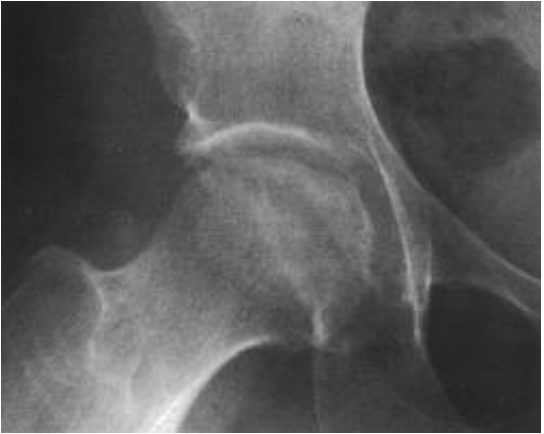

В ортопедии и травматологии рентгенологическое исследование применяют для диагностики деформирующего коксартроза, артритов, асептического некроза головки бедренной кости, костных новообразований, вывихов, переломов шейки бедренной кости и так далее. Например, невозможно получить послойное изображение тканей, из-за чего врачи не могут определить точную локализацию патологических изменений.

Симптомы и синдромы, выявляемые при рентгенологическом исследовании:

- сужение суставной щели. Признак дистрофических изменений суставного хряща. Этот симптом выявляют у больных с деформирующим остеоартрозом и хроническим артритом;

- остеопороз. Снижение плотности костей. Характеризуется уменьшением числа костных лучей в единице объема костной ткани. Патология развивается в пожилом возрасте. Сам по себе остеопороз протекает бессимптомно, но в результате часто развиваются деформирующий остеоартроз и переломы шейки бедра;

- разрушение. Возникает в результате инфекционного процесса. Характеризуется разрушением участков кости с дальнейшим замещением их гноем, грануляциями или опухолевой тканью. Наличие деструкции может свидетельствовать о парапротезной инфекции, остеомиелите, злокачественных новообразованиях;

- некроз. Неинфекционный некроз костной ткани. Чаще всего участки некроза появляются в области головки бедренной кости. Причина – возрастное ухудшение кровотока и обмена веществ.

Вывих ТБС. Головка бедренной кости смещена и выходит за пределы вертлужной впадины.

Сломать. Это выглядит как строка или столбец. Чаще локализуется в области шейки бедренной кости.

Некроз. Место некроза кажется более плотным, из-за чего выделяется на фоне окружающих тканей.

разрушение. На рентгене выглядит как костный дефект. Свежие деструктивные очаги имеют неровные контуры, старые ровные и сжатые.

Деформирующий остеоартроз. На ранних стадиях рентгенологические признаки отсутствуют. Позже о патологии говорит сужение суставной щели.